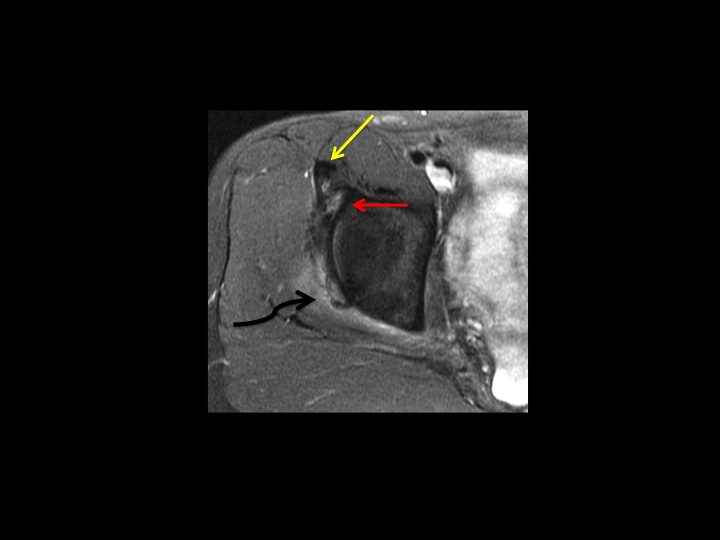

26F dancer with acute injury and hip pain

Yellow and Red arrows indicate partial tears at the origin of the direct and indirect head of the rectus femoris, respectively. The white arrowheads show acetabular stripping of the indirect head and iliofemoral ligament. I presume, due to the acuity of injury, that the dark amorphous signal (curved black arrow) is hemorrhage....but can I know that with certainty without either XR or US? I often have difficulty, particularly in shoulder, when I think there might be punctate calcific deposits that are unlikely to be visible by XR: would you recommend US in all such cases? (and, btw, I dont think the labrum is normal, but doubt thats her main problem...I suspect this will all heal with rest)